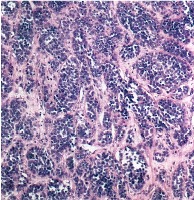

This is an AI laboratory project by Linette Dannah Cartagena, a second year medical student. Ovarian cancer can be classified into four main types: epithelial tumors, germ cell tumors, stromal tumors, and small cell carcinoma of the ovary. This model aims to recognize each type through AI. All one has to do is to simply by upload a photo of the histological slide.